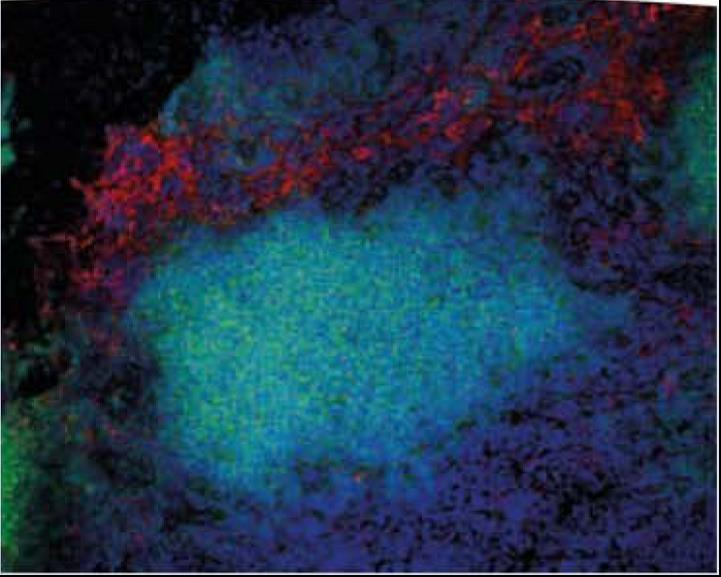

小鼠淋巴结的免疫荧光染色;巨噬细胞用anti F4/80(MCA497PE)染成红色,B细胞用anti CD79b(MCA1821A488)染成绿